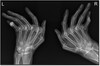

• Spiral